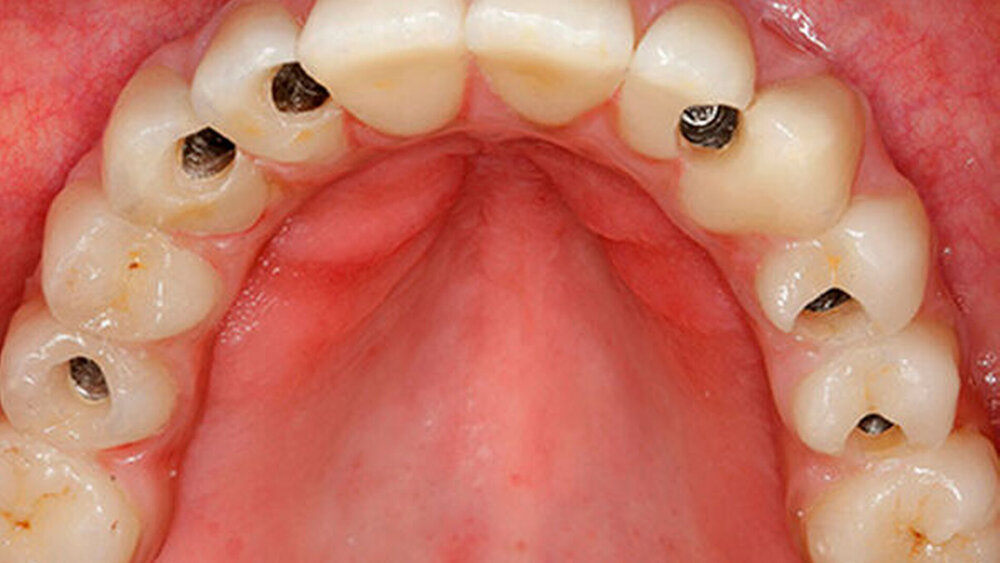

Eine 67 Jahre alte Patientin stellte sich mit dem Wunsch einer Oberkiefersanierung in unserer Praxis vor. Ihre Restzähne waren aufgrund von Parodontitis und funktioneller Überlastung nicht mehr erhaltungswürdig. Wir ließen sie bis kurz vor der definitiven Versorgung als strategische Pfeilerzähne für die Interimsprothese in situ.

Selbst wenn das Provisorium basal sehr gut konfiguriert, poliert und auch perfekt verschraubt wird, kann es in den ersten Wochen nach der OP Entzündungen provozieren. Denn zwischen Provisorium und Wunde bleiben häufig Speisereste hängen, die schwierig zu entfernen sind. Die Interimsversorung vor der iSy-Brücke lässt sich dagegen einfach zur Reinigung herausnehmen.

Bei Interimsversorgungen bis zur Osseointegration und der sich anschließenden prothetischen Phase (etwa drei bis vier Monate). Werden die inserierten und freigelegten Implantate mit einem Langzeitprovisorium versorgt, bleibt dieses bis zur Adaptation sechs bis acht Monate in situ. Bis der All-on-four-Patient sein verschraubtes Provisorium richtig adaptiert hat, vergehen auch fünf bis sechs Monate. Die Dauer des Provisoriumtragens unterscheidet sich also nicht wesentlich.